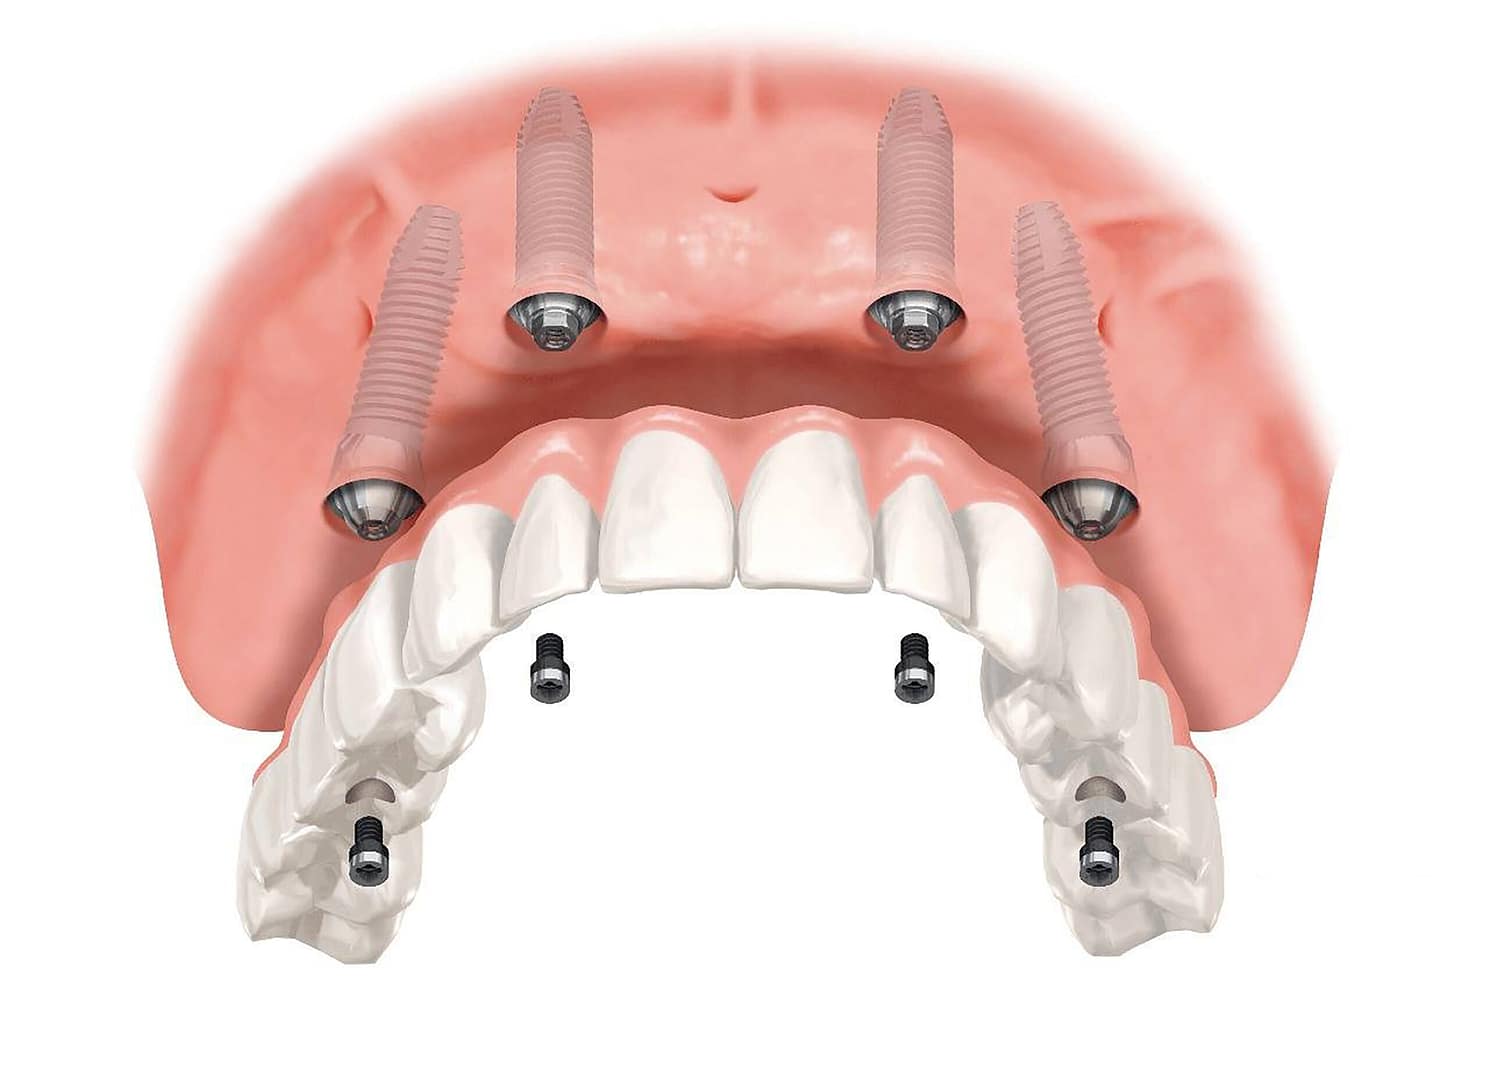

- Estabilidad: fijados al hueso, no se mueven como las prótesis removibles.